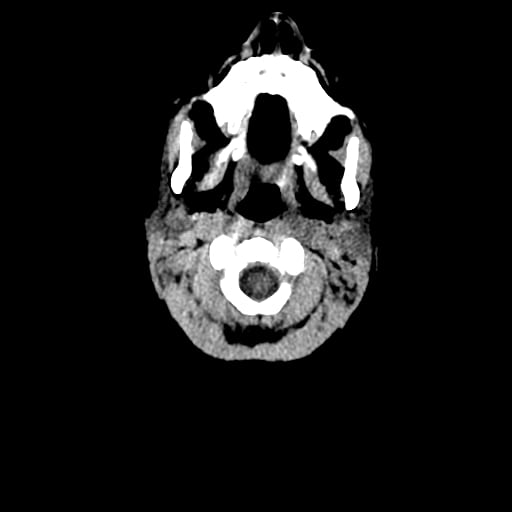

Age: 1

Sex: Male

Indication: Fall